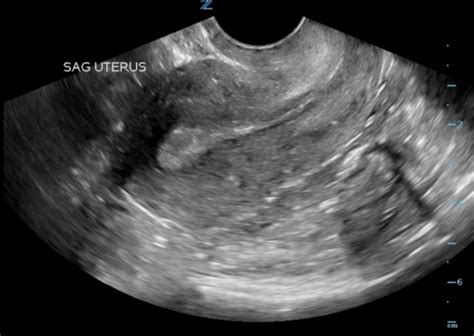

An Ultrasound at 4 Weeks is typically performed transvaginally, as it provides a clearer image of the uterus and the developing embryo at this early stage. The procedure is non-invasive and generally painless, although some women may experience slight discomfort. The ultrasound technician will use a wand-like device covered with a condom and lubricated with gel, which is inserted into the vagina to capture images of the uterus.

• Gestational Sac: This is the first structure visible on the ultrasound, appearing as a small, fluid-filled sac within the uterus.

• Yolk Sac: As the gestational sac develops, a yolk sac will form within it. This sac provides essential nutrients to the embryo before the placenta takes over.

• Embryo: At 4 weeks, the embryo itself is very small, often measuring less than 1 mm. It may not be visible on the ultrasound, but the presence of the gestational and yolk sacs is a positive sign.